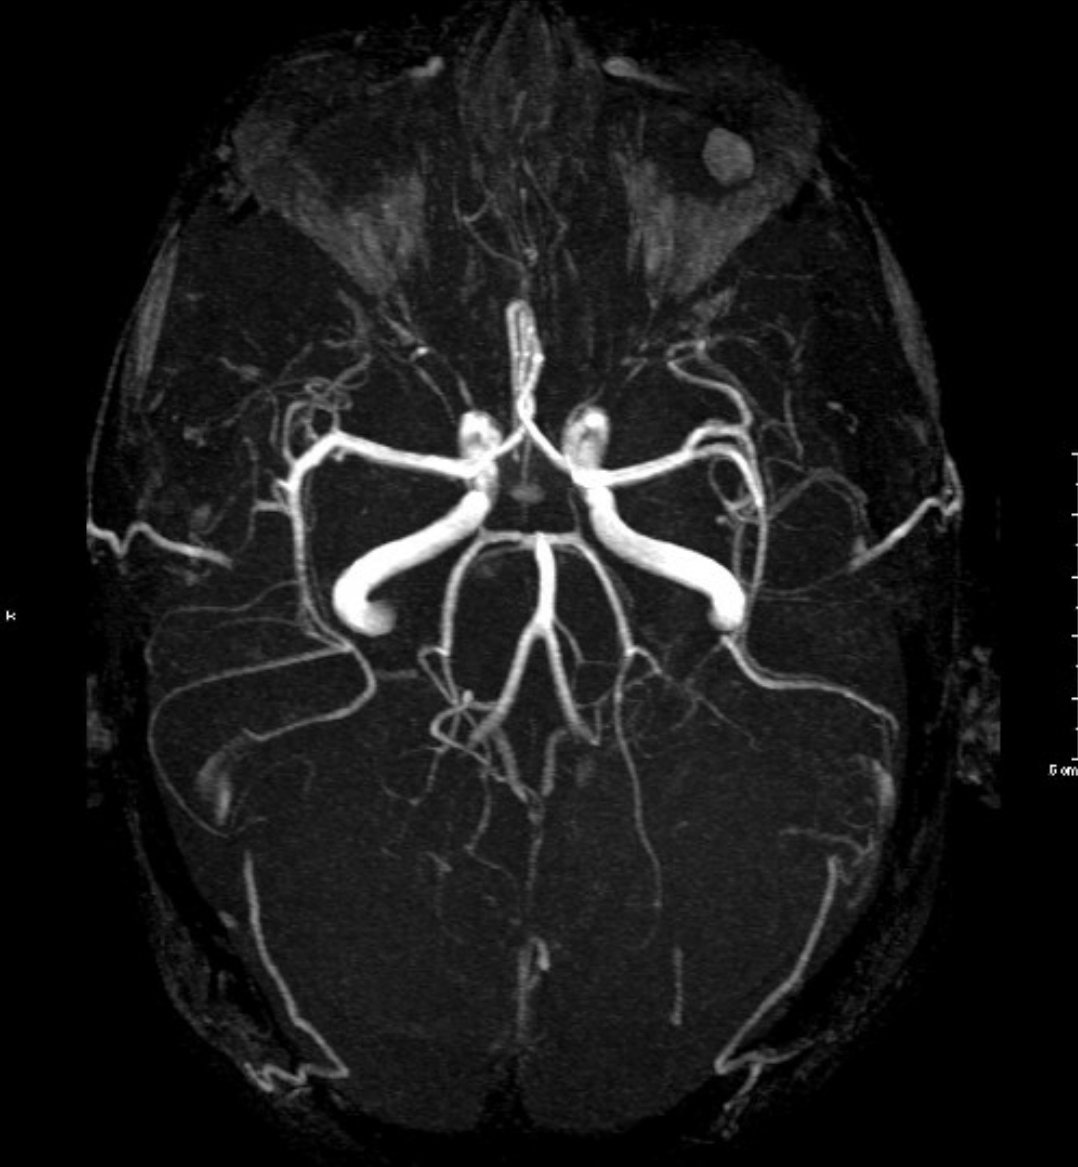

💥الفحوصات

🧠تحاليل دم

🧠اشعه مقطعيه للمخ

قد نحتاج

🧠اشعه بالصبغه

🧠اشعه تداخليه بالقسطرة للتشخيص والعلاج

💥الفحوصات الاساسيه

🧠اشعه مقطعيه/رنين للمخ

🧠دراسه الشرايين المغذيه للمخ

تختار حسب مكان الجلطه/وظائف الكلى/التوفر

(مقطعيه بالصبغه/رنين مغناطيسي/اشعه صوتيه للرقبه/قسطرة تداخليه)